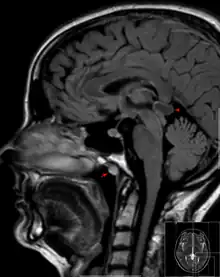

Tornwaldt cyst imaged on sagittal MRI (FLAIR). The cyst appears hyperintense in the midline of the nasopharynx (arrow). In this case there is also a cyst of the pinealis gland (arrowhead) showing a signal intensity slightly higher than the CSF.

A Tornwaldt cyst also spelt as Thornwaldt or Thornwald cyst[1] is a benign cyst located in the upper posterior nasopharynx. It was first described by Gustav Ludwig Tornwaldt. It can be seen on computed tomography (CT) or magnetic resonance imaging (MRI) of the head as a well-circumscribed round mass lying in the midline. In most cases, treatment is not necessary. Indications for treatment include symptomatic lesions, large lesions (>1 cm), or lesions adjacent to the eustachian tube orifice.[2]